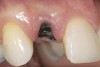

Treatment consisted of flapless extraction, socket grafting using mineralized bone allograft (Puros®, Zimmer Dental Inc, Carlsbad, CA), and a pedicled connective tissue graft36,37(Figure 11). Five months post-surgery, reentry was accomplished via a mid-crestal and labial sulcular incision. A crestal plasty was per- formed before implant placement into type II bone (Figure 12 and Figure 13). An immediate provisional was used for 3 months (Figure 14) before final crown fabrication (Figure 15).

Figure 12  Stage I surgery (implant shown with healing abutment), 4 months after extraction and socket graft.

Figure 12

Figure 13  Primary flap closure.